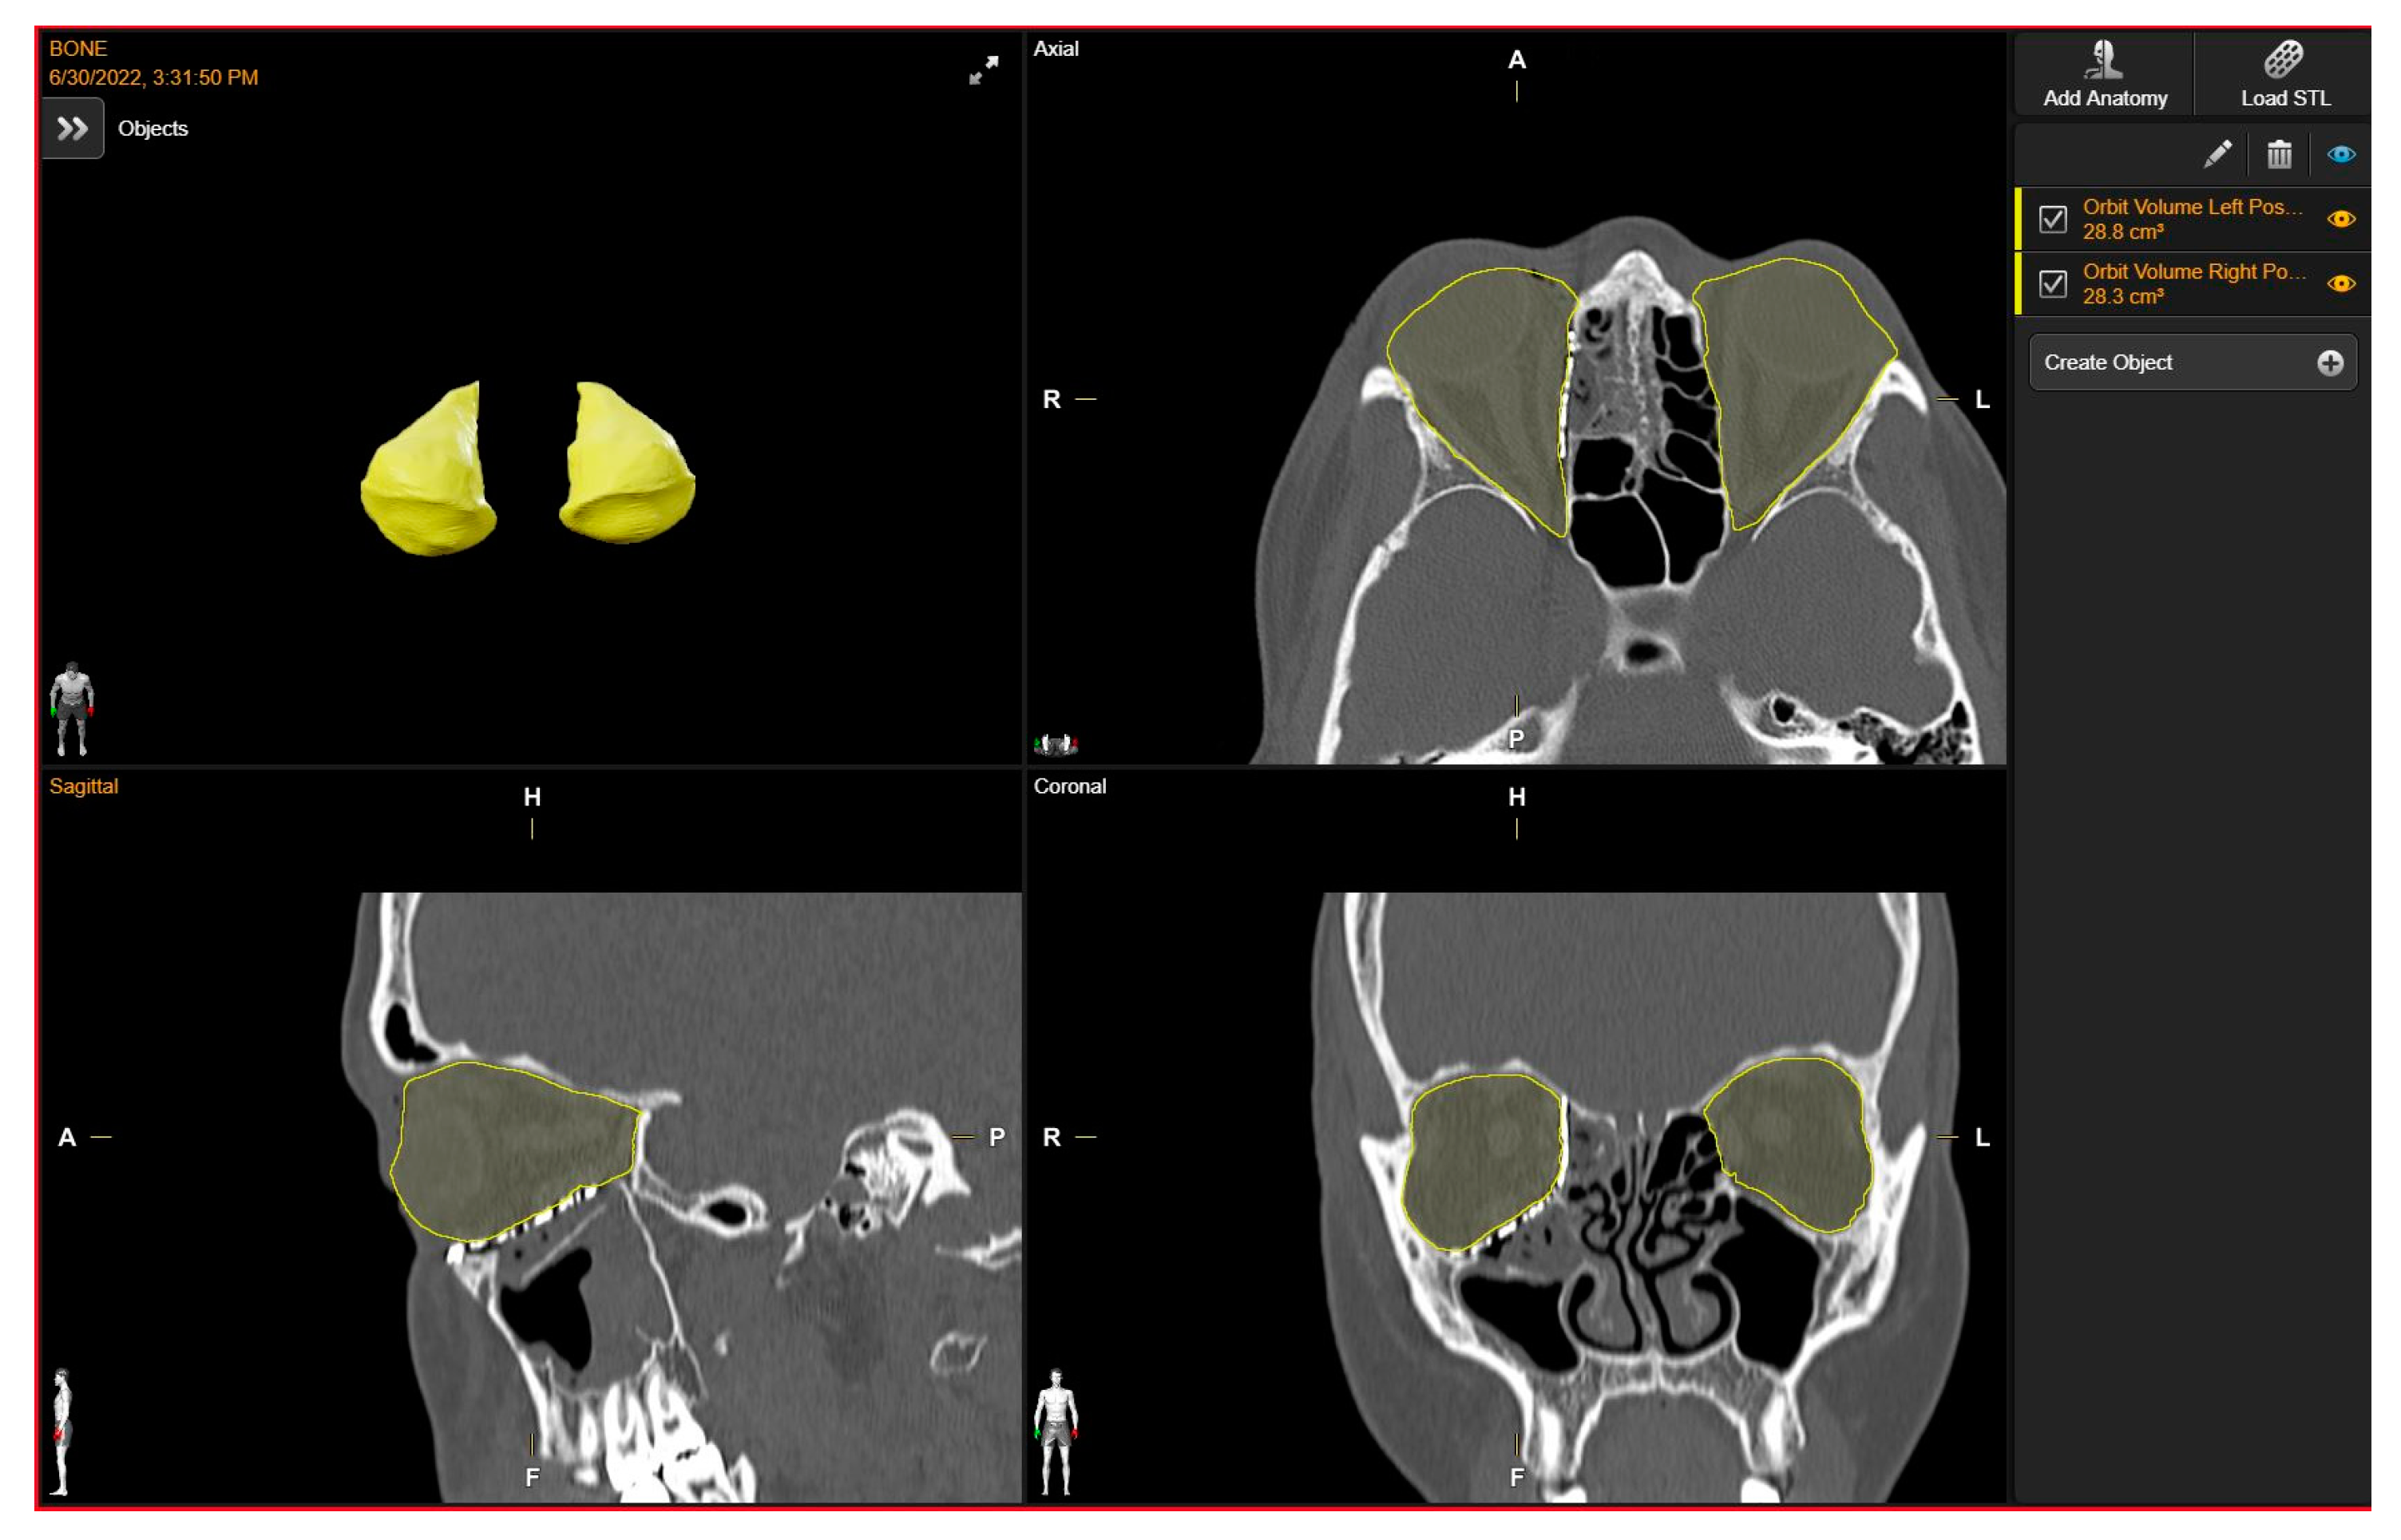

To evaluate the correspondence between the postoperative CT scan and the Virtual Surgical Planning (VSP), the process of overlaying postoperative CT scans onto preoperative planning images was executed through the “Image Fusion” tool within the software. “Brainlab Elements Contouring”, version 4.0 (Brainlab, Feldkirchen, Germany) (Figure 2), which creates an automatic alignment of preoperative images and postoperative CT scans. Subsequently, through visual inspection, areas where the boundaries of the superimposition were not perfectly aligned were carefully examined. In these regions, the mismatch between the postoperative CT plate and the simulated virtual positioning of the mesh was manually measured.

This manual calculation involved identifying points of deviation between the planned and actual positions and measuring the maximum difference observed. This difference, termed the “maximum error”, was then recorded for further analysis.

Figure 2. The overlaying of postoperative CT scans onto preoperative planning images.